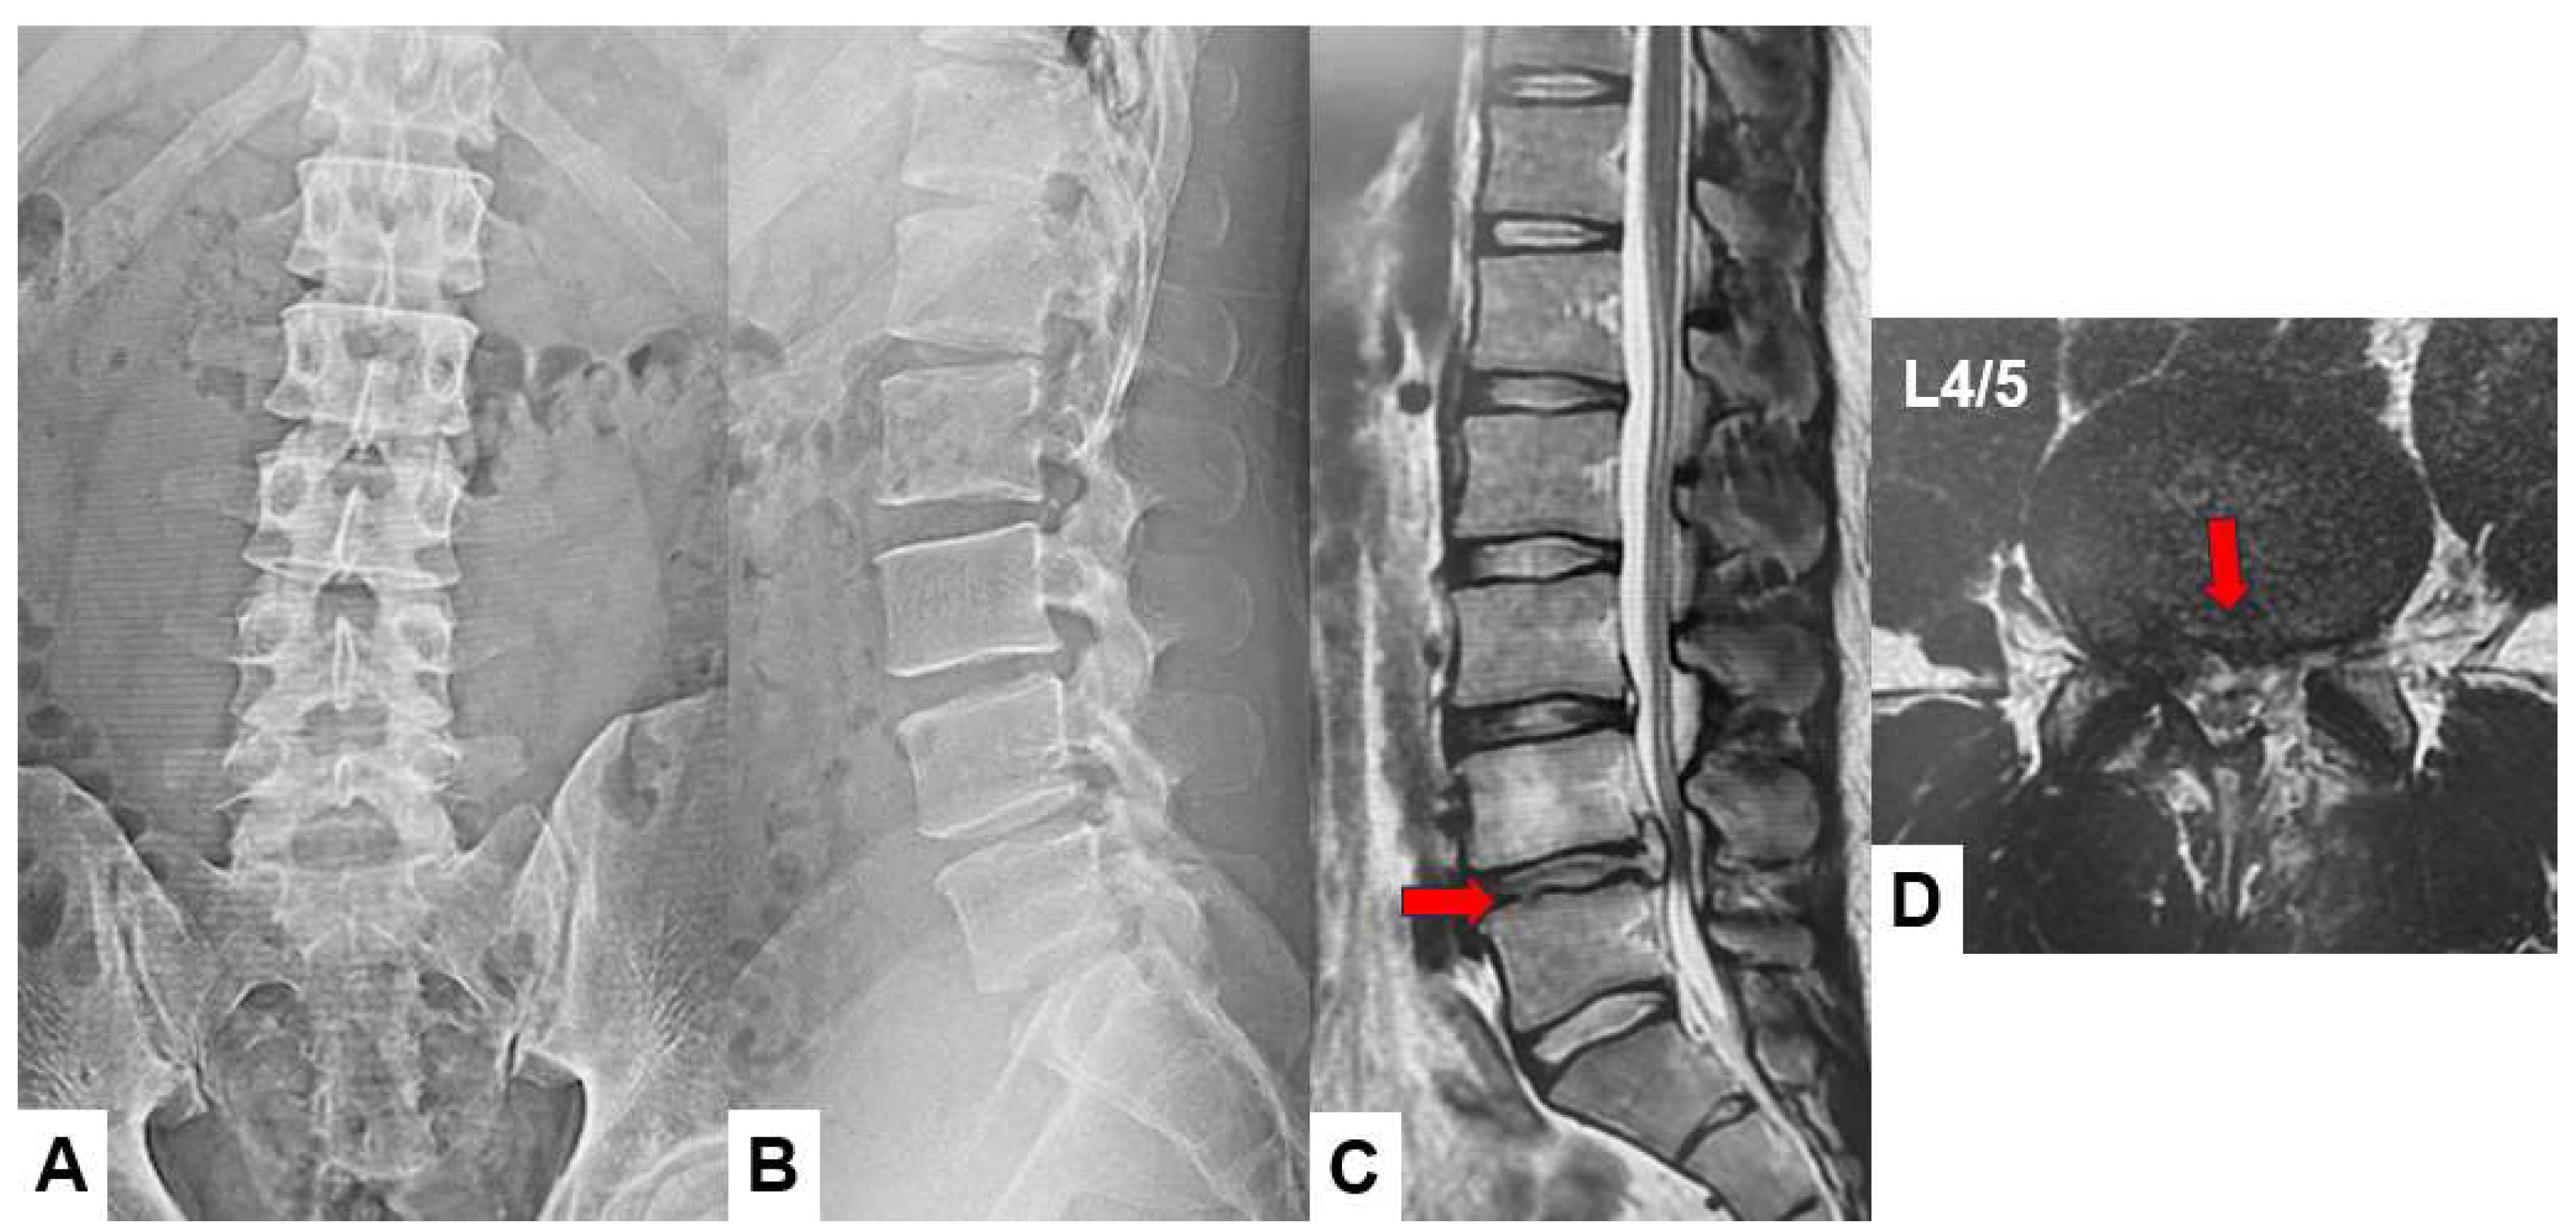

Preoperative anteroposterior lumbar radiogram indicates slight instability at L4/5 level (Figure 1). Preoperative lumbar 3D CT showed lumbar scoliosis due to disc herniation. Preoperative MRI indicated L4/5 central disc herniation and compressing bilateral L5 nerve roots (Figure 2).

Figure 2. Preoperative CT and MR imaging, A: Mid sagittal 3D reconstruction CT, B: 3D CT, .C: T2 weighted mid-sagittal MR imaging, D: T2 weighted axial MR imaging at L3/4, E: T2 weighted axial MR imaging at L4/5, A large lumbar disc herniation was observed (red arrows).